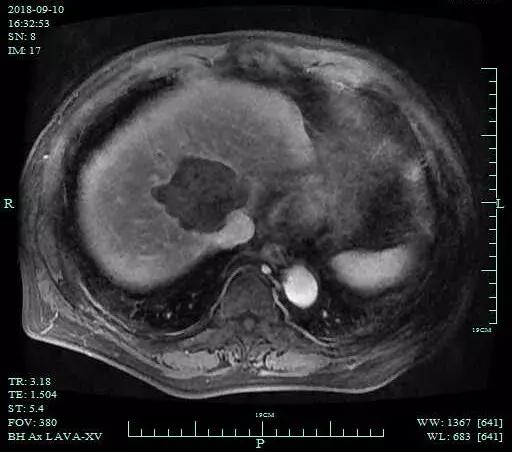

术后CT和MRI复查,显示粒子植入位置良好,消融病灶完全灭活。

术后MR-增强序列病灶整体无增强